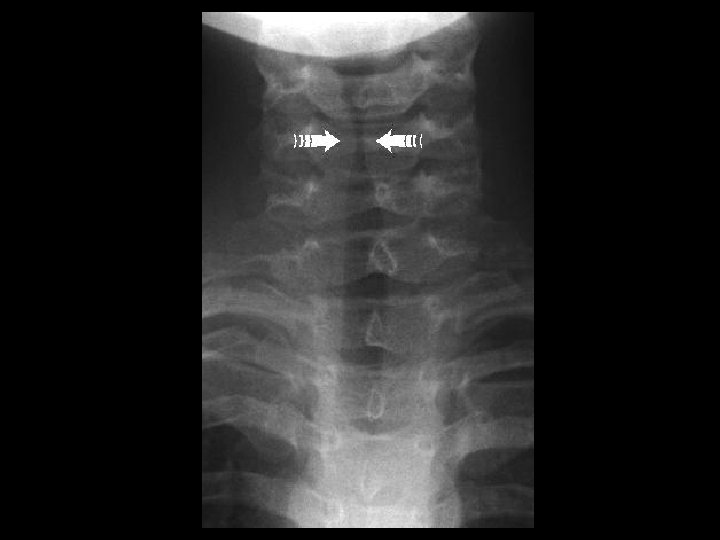

Laryngotracheobronchitis • Findings: – Narrowing of the subglottic airway = “steeple sign” – a. k. a. Croup – viral infxn (parainfluenza) but may be bacterial (S. aureus) – Check lateral film for acute epiglottitis (25% have subglottic narrowing) • ddx: – epiglotitis – membranous croup